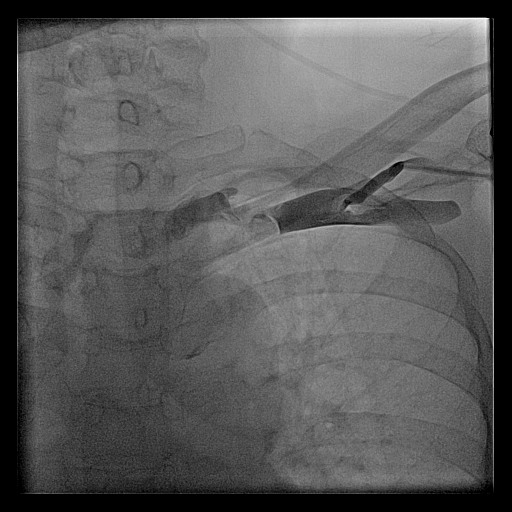

Subclavian vein

Subclavian vein puncture

subcl_puncture.jpg

Subclavian vein - pros and cons

• ( + ) More people are familiar

• ( + ) Anatomical landmarks sufficient

• ( - ) Risk of pneumothorax

• ( - ) Risk of lead crush